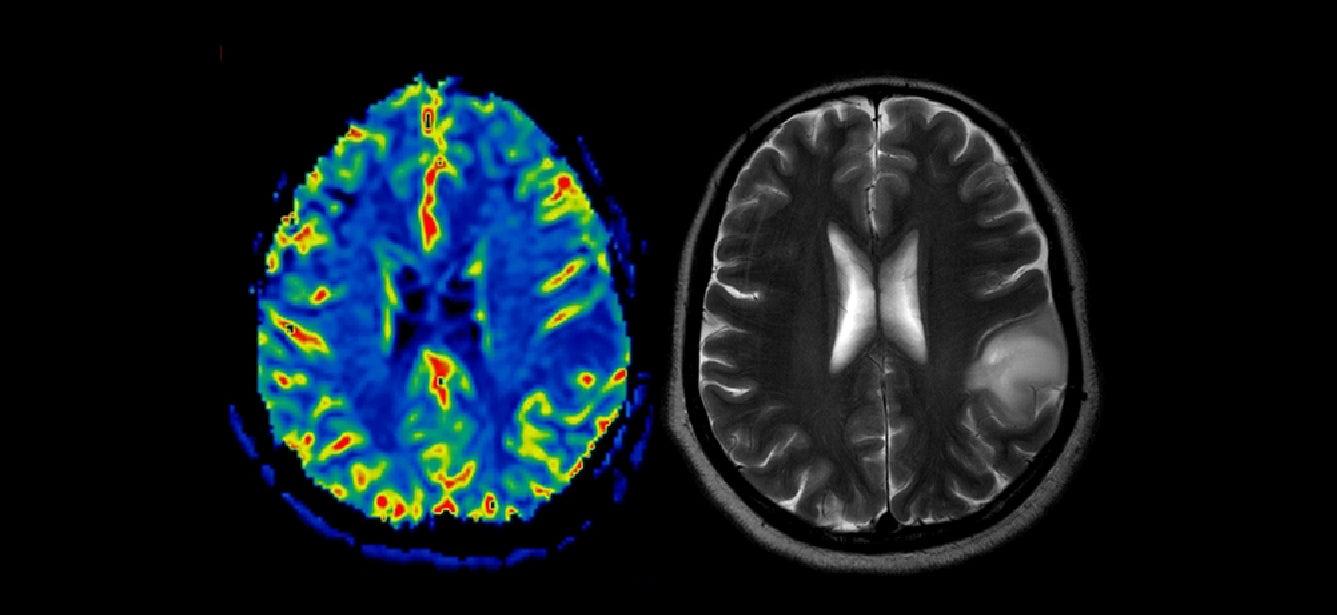

With Alzheimer's, Kisunla targets and binds to amyloid-beta plaques in the brain. These plaques are clumps of protein fragments believed to play a key role in the development and progression of the disease. By binding to these plaques, Kisunla helps to clear them from the brain, potentially slowing the detrimental cognitive effects.

Kisunla is specifically approved for people with early symptomatic Alzheimer's disease. This includes patients who are experiencing mild cognitive impairment or mild dementia, the population in shich treatment was studied in the clinical trials. To qualify for Kisunla, patients usually must undergo a thorough evaluation, including cognitive testing and brain scans or imaging, such as a PET scan, to confirm the presence of amyloid plaques. Other tests that can be used to determine the presence of plaques include spinal fluid and blood plasma.

Like any medication, Kisunla can cause side effects. The most common ones seen in patients were headache and ARIA (amyloid-related imaging abnormalities), which can include swelling or small areas of bleeding in the brain. These imaging changes will be monitored closely by health care providers to manage any potential risks, especially during the early months of treatmetn when ARIA is most likely to occur.